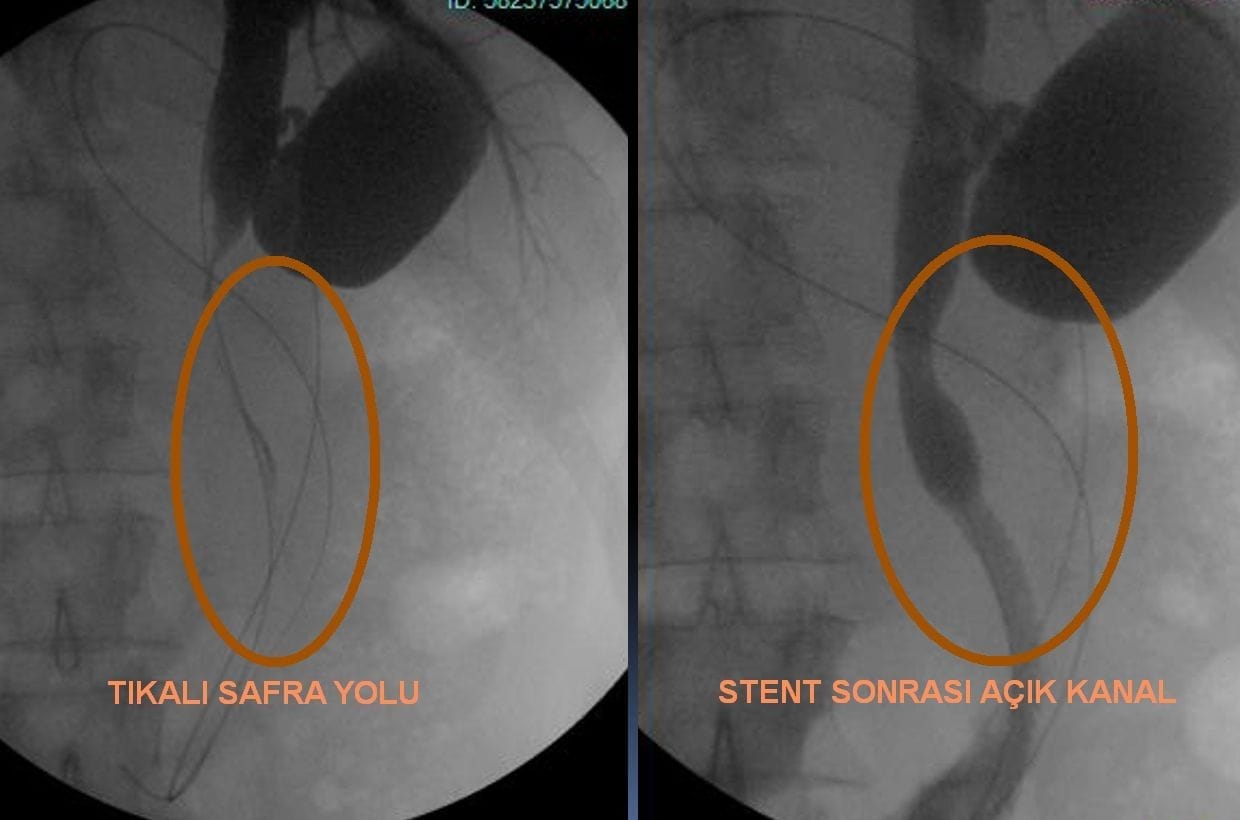

Plasarea stentului se realizează folosind tehnici de radiologie intervențională, așa cum se utilizează în radiologia intervențională. Procedura, efectuată sub anestezie, implică o serie de pași. Mai întâi, se evaluează starea căilor biliare printr-o procedură de imagistică, cunoscută sub numele de Colangiografie Transhepatică Percutanee (PTK). PTK este folosită pentru a vizualiza detaliat starea căilor biliare, pentru a identifica locația și cauza blocajului. În timpul acestei proceduri, o ac fin este introdus prin piele în ficat, iar un agent de contrast este injectat în căile biliare pentru a obține imagini radiologice. Aceste imagini clarifică anatomia căilor biliare și detaliile blocajului, permițând astfel planificarea tratamentului adecvat. Aceasta este o etapă critică pentru identificarea locației și a cauzei blocajului. După imagistică, se utilizează un tub fin și un ghid pentru a ajunge la zona blocată. Tubul este avansat până la locul blocajului, iar stentul este plasat acolo. Odată ce stentul este deschis, blocajul este eliminat și fluxul normal de bilă poate continua.

Tratamentul icterului obstructiv implică plasarea unui stent biliar, o opțiune importantă. Acest tratament are ca scop eliminarea blocajelor care împiedică fluxul bilei de la ficat la vezica biliară și, ulterior, la intestinul subțire. Blocajele din căile biliare sunt, de obicei, cauzate de pietre biliare, tumori sau inflamații. Plasarea stentului deschide mecanic aceste blocaje, restabilind astfel fluxul biliar normal.